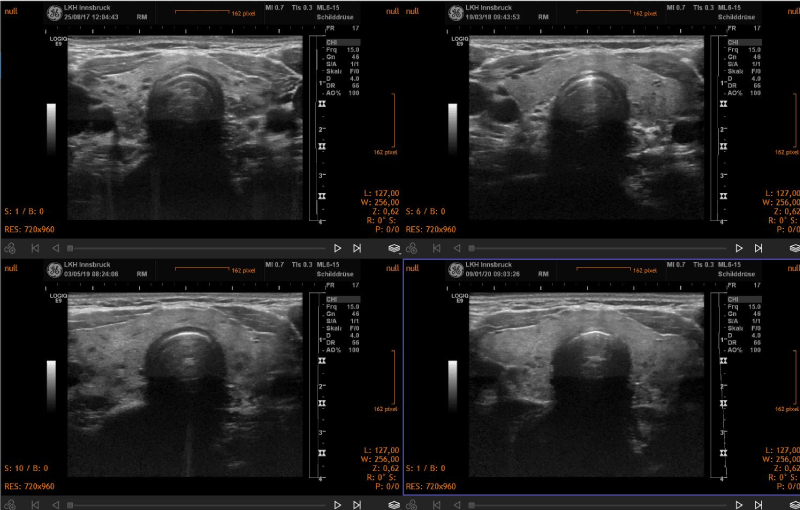

Over a period of 18-24 months, signs of improved morphology and decreased vascularization were seen. In general, the morphological changes included a reduction of thyroid volume and a normalization of the structure of the gland in cases of subacute thyroiditis. Two representative clinical cases are shown in the figure 1. In hyperthyroidism the pattern of increased vascularization of the gland normalized during treatment (Figure 2). Thyroid morphology also showed improvement (Figure 3).

Figure 1. Sequential demonstration of normalization of thyroid morphology in a case of subacute thyroiditis. The initial study (upper left panel) revealed an inhomogeneous structure with many areas with reduced echogenicity. The final image (lower right panel) shows a normal thyroid morphology